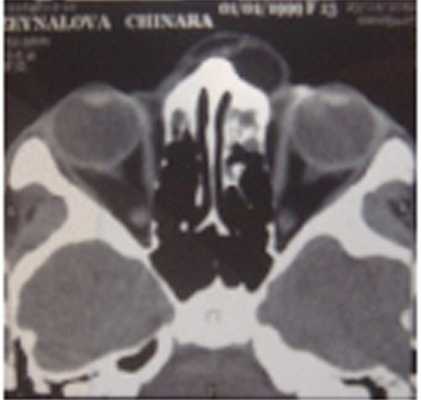

Все больные проходили КТ-исследование, благодаря которому можно изучить структуру самой опухоли, а также состояние подлежащих костей и степень распространения в орбиту. На К.Т. выявлялось образование округлой или овальной формы с четкими и ровными контурами. У всех кист отчетливо прослеживалась капсула, а также наличие серозного содержимого (рис. 5, 6). Узурацию костной стенки, описанную в литературе не встречали.

Рис. 5. Компьютерная томограмма дермоидной кисты внутреннего квадранта орбиты.

Рис. 6. Компьютерная томограмма дермоидной кисты наружного квадранта орбиты.